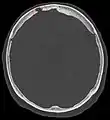

Non-contrast CT scan of the head showing an arachnoid granulation